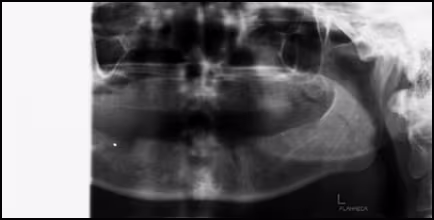

The third category of technical errors in panoramic radiography involves shoulder and receptor contact due to short neck and/or thick shoulder anatomy and lack of clearance between the shoulder and the receptor and/or x-ray head. Contact may result in stoppage or improper machine rotation, patient movement, image artifacts or partial image production.

Figure 68. Shoulder contact on the patient’s right caused the machine to stop resulting in an incomplete or partial image.

Figure 69. Shoulder contact on the patient’s right side caused the patient to move in response.